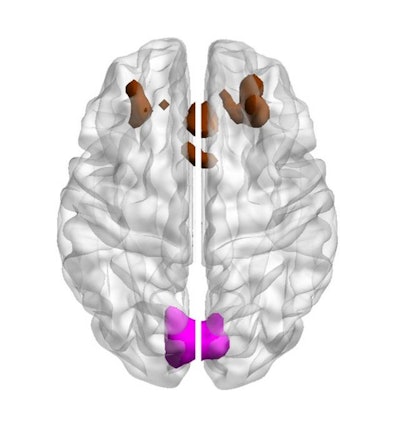

Image showing bilateral cuneal (magenta) and frontal cortex (brown). Courtesy of eLife/University of Cambridge.

Overall, the team found that participants' ability to solve the puzzles decreased with age. But the researchers also reported that in some older people, two areas of the brain showed greater activity and correlated with better performance on the puzzle task: the cuneus, at the rear of the brain, and a region in the frontal cortex.

"Although it is not clear exactly why the cuneus should be recruited for this task, the researchers point out that this brain region is usually good at helping us stay focused on what we see," the university noted in its statement. "Older adults often have a harder time briefly remembering information that they have just seen, like the complex puzzle pieces used in the task. The increased activity in the cuneus might reflect a change in how often older adults look at these pieces, as a strategy to make up for their poorer visual memory."